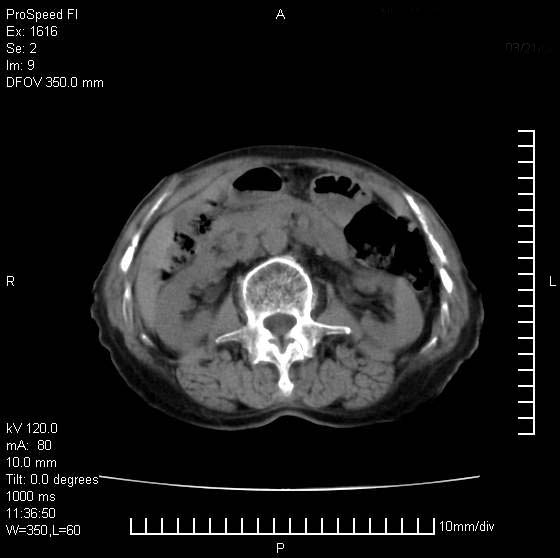

患者无明显临床症状,肝左叶发现一个圆形密度不均的低密度灶,边界较清楚,大小37x45mm,ct值35-70,患者犹豫做增强,如有增强片,我再发上,现先请各位老师会诊.

左肝外叶可见较大圆形低密度影,病灶可见较光整清晰边界,病灶内可见多量条状稍高密度影,右肝前叶亦可见圆形结节状低密度影,边界清晰,密度均匀,考虑1肝多发囊肿,左肝囊肿内出血2肝包虫病3左巨块型肝癌出血合并右肝转移或合并右肝囊肿

左肝外叶可见较大圆形低密度影,病灶可见较光整清晰边界,病灶内可见多量条状稍高密度影

考虑:肝包虫病

肝左叶类圆形低密度影,内可见略高密度影,边界清晰周边可见环形低密度带,考虑肝腺瘤可能,建议增强扫描除外肝血管瘤与肝癌

hcc(巨块型)伴出血,突破肝包膜,肝胃韧带内,腹主动脉旁淋巴结转移;肝硬化

肝左叶不均匀占位,内有斑片状高密度出血灶,内侧缘似有假包膜,腹主动脉周围及肝门区结构紊乱,似有增大淋巴结,考虑:肝左叶hcc并淋巴结转移。建议增强扫描除外其他。